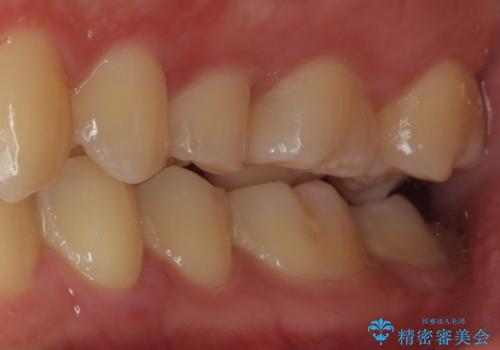

歯に穴が開いた セラミックインレー修復

- 当院でインビザラインによる矯正治療が終わった患者様です。

矯正治療終了時歯に穴が開いたとのことで、治療を希望されました。

拡大鏡視野化にて、虫歯を除去し、セラミックインレー(セラミックの詰め物)に適した形に整えました。